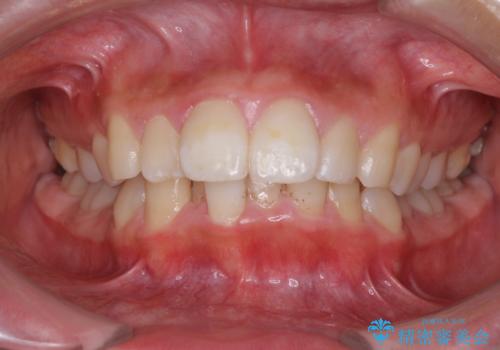

口が閉じられない 抜歯矯正で口元をスッキリと

- 上下の出っ歯を気にして来院された患者様です。

口元を積極的に引っ込めるために、上下左右の第一小臼歯を4本抜歯することとしました。